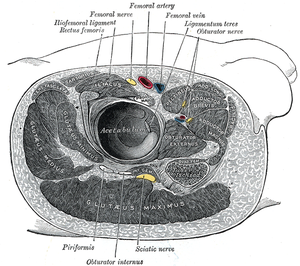

Obturator nerve entrapment

Background

- Follows trauma and pelvic fractures

Clinical Features

- Pain in groin and down inner thigh

- Aggravated by movement of the hip